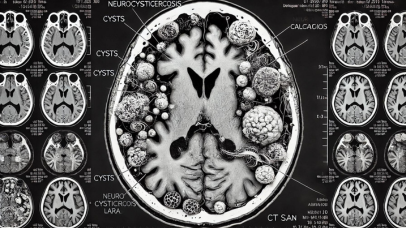

Journal of Commissure is a peer-reviewed publication dedicated to advancing the field of neurology through high-quality research and clinical studies. Established in 2024, our journal serves as a vital resource for neurologists, neuroscientists, and healthcare professionals worldwide.

Neuroimaging, Neuropathology vnmishraneuro@bhu.ac.inSubscribe to our newsletter